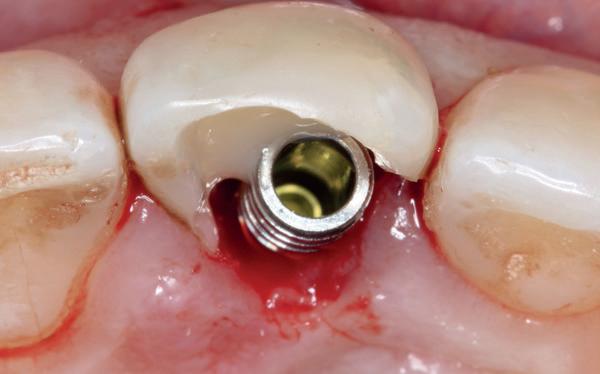

Tijdens het verwijderen van het membraan is het botvolume klinisch waarneembaar en blijkt dat er voldoende bot is om het implantaat te kunnen plaat-

sen. Tijdens deze procedure wordt er ook een free gingival graft van het palatum gehaald. Deze wordt buccaal aangebracht van de 22 en 23 om zo de recessie zoveel mogelijk te bedekken en de papil tussen de 22 en 23 van meer volume te voorzien.

De flap en graft worden met poly-propelene 6.0 hechtingen gefixeerd. De tijdelijke reconstructie wordt herplaatst (foto 17-20).